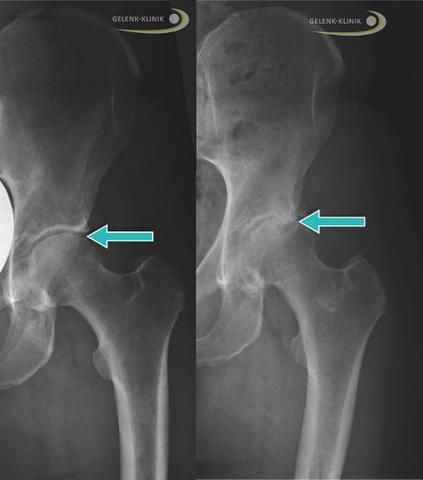

Um eine Coxarthrose festzustellen, wird eine gründliche Untersuchung durchgeführt und eine Röntgenuntersuchung im Stehen durchgeführt. Zusätzlich kann ein Ultraschall eingesetzt werden, um Veränderungen der Weichteile im Hüftgelenk festzustellen.

Die Diagnose einer Coxarthrose erfolgt durch eine gründliche Untersuchung und Befragung des Patienten sowie durch Röntgenaufnahmen im Stehen, um die Hüfte unter Belastung zu beurteilen. Eine Ultraschalluntersuchung kann zusätzlich Wassereinlagerungen und Veränderungen der Weichteile im Hüftgelenk feststellen.

Um Coxarthrose zu diagnostizieren, führen wir zunächst eine gründliche Untersuchung durch und befragen Sie zu Ihren Symptomen. Eine Röntgenuntersuchung im Stehen ist der maßgebliche Befund zur Bestätigung einer Coxarthrose.